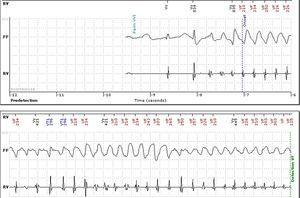

No abnormalities were detected on laboratory tests and transthoracic echocardiography revealed no significant alterations. The 12-lead electrocardiogram (ECG) performed at the cardiology consultation showed sinus rhythm and significant QTc prolongation (500–565 ms) (Figure 1). She was taking carvedilol 12.5 mg twice daily but the dose could not be titrated due to symptomatic hypotension. In view of the result of the previous tilt test and the non-specific symptoms, it was decided to implant an event recorder. The patient reported several episodes of pre-syncope, which corresponded to periods of sinus tachycardia, and in one of these nonsustained polymorphic ventricular tachycardia (VT) was recorded (Figure 2). It was accordingly decided to implant an implantable cardioverter-defibrillator (ICD). Around a month after the procedure remote monitoring recorded an appropriate shock for polymorphic VT (Figure 3). Her beta-blocker therapy was changed to propanolol.